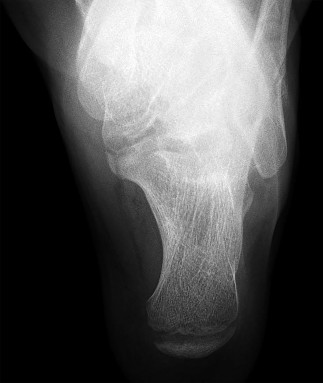

A 3-year-old girl, who is at the 95th percentile for weight and began walking at 9 months of age, presents with progressive bilateral genu varum.

Radiographs reveal an abrupt medial beaking of the proximal tibial metaphysis and a metaphyseal-diaphyseal angle (Drennan's angle) of 18 degrees. What is the most likely diagnosis?